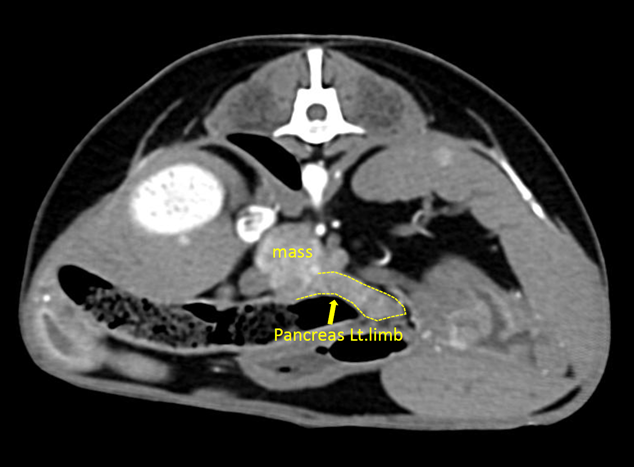

(๊ทธ๋ฆผ3. ๋น์ฅ ๋ค๋ฐ์ฑ ๋ณ๋ณ)

(๊ทธ๋ฆผ4. ์ ์ ๋ ์กฐ์ง๋ค : ์ธ์๋ฆฐ์ข

, ๋น์ฅ๋ฆผํ์ , ๊ฐ๋ฆผํ์ , ๋น์ฅ)